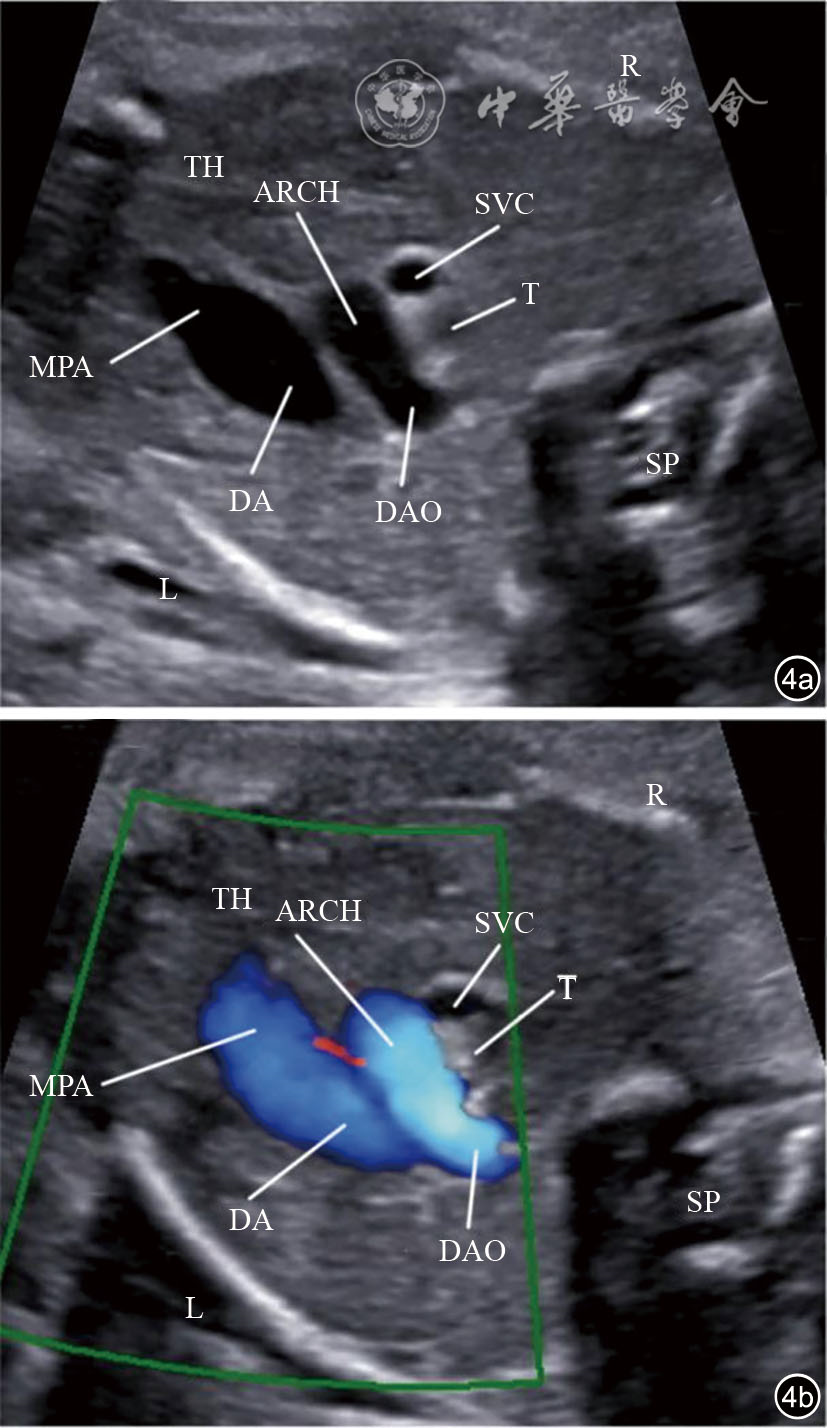

图4 三血管气管切面超声图像和彩色多普勒血流成像(CDFI)。图a为三血管气管切面;图b为三血管气管切面CDFI 注:ARCH为主动脉弓;SVC为上腔静脉;MPA为主肺动脉;DA为动脉导管;T为气管;TH为胸腺;SP为脊柱;L为左侧;R为右侧